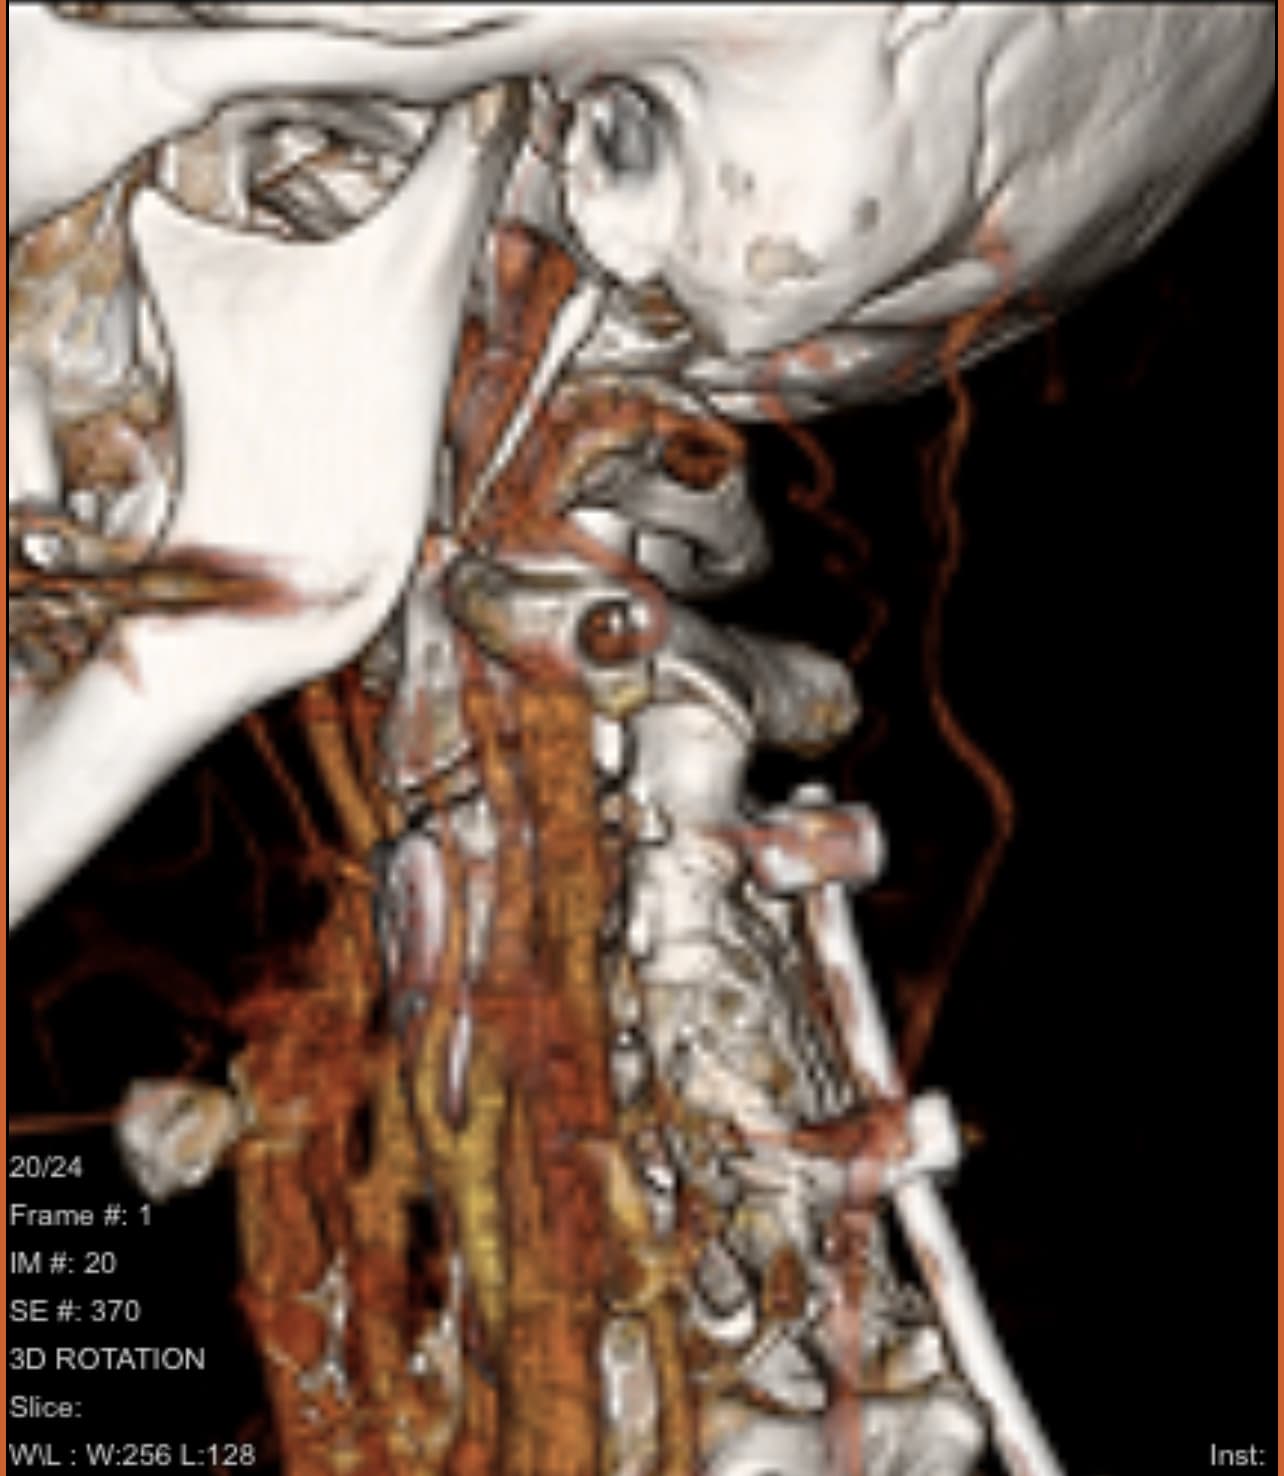

Obviously not a doctor, but it doesn’t look as if your IJV is too compressed in those images, this can look very different though in the axial imaging that @TML has been helping us with… The hyoid does look quite close to the bifurcation of the ICA & ECA in this image:

But sometimes again it looks different in the axial views…it could well explain how you’re feeling if this is the issue :hugs:

I agree w/ @Jules that your IJVs look compressed & especially the left side where it just disappears. I can’t tell about what your hyoid is doing though. Your styloids both look quite long, but I understand your left side has been partially removed so is shorter now. I expect it is still putting pressure on your IJV which is causing some of your symptoms. I’m sorry the doctor who did your surgery didn’t do a great job.

Here are two of your images that show your hyoid bone. I marked them so you can see where it is. One is from the front & the other is from the right side. Unfortunately, there isn’t a picture of the hyoid from the left side. In the picture of the right side, your IJV blocks the greater horn of the hyoid so we can’t see if it’s poking your carotid arteries there. Can you also upload a picture that shows your hyoid from the left side?